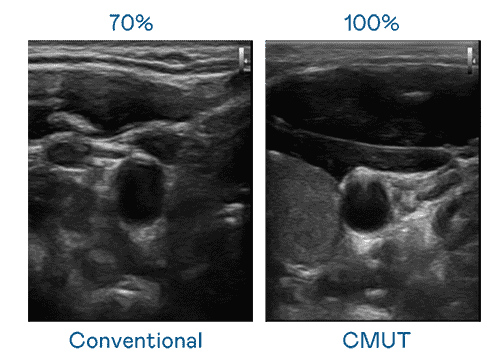

CMUT 技术是一种用电容式微机电元件来产生超音波讯号的技术。。。。与传统 PZT 压电式技术相比,,,CMUT 频宽增加 30%,,,更宽频的超音波讯号让影像解析度大幅提升,,,,是实现高影像品质医疗超音波扫描、、、促进精准医疗发展的关键技术。。

大频宽带来超清晰影像

超音波影像的解析度高低,,,,首先取决于探头能发出的讯号频宽。。。。彩霸王 CMUT 可提供高清晰的超音波讯号,,提供高频宽、、、高灵敏度、、、影像纹理细节更高的超音波影像,,,协助医护人员缩短影像判读时间及利用精准的医疗影像进行诊断。。